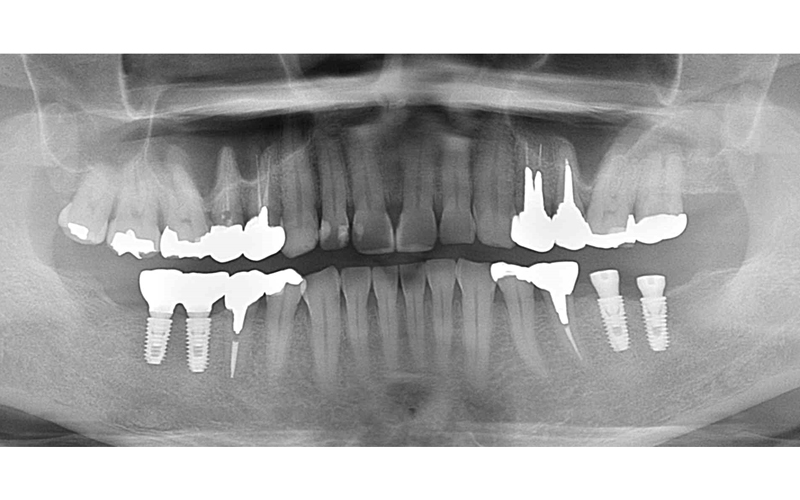

上部構造セット後

| 備考 | 【治療詳細】 右下の6番延長ブリッジの根が太く長い土台の金属が入っており、歯根破折しておりました。 左側の7番も同様に歯根破折しておりました。 左側インプラント治療後。患者さん希望の為、インプラント体1本に対して2本分の被せ物で補綴。 案の定、内部のネジの緩みが何度か発生。 右下が保存不可能になった為、インプラント2本埋入。 右下のインプラントが経過良く、左下のインプラントの追加を希望されましたので、被せ物をいったん除去して追加埋入。 補綴完了後の口腔内。現在最初のインプラント埋入から5年経過しておりますが、経過良好です。 左下6番のみ被せ物の内部に金属を使用していますが、他はフルジルコニア。 アクセスする穴にレジンを使用しています。 |